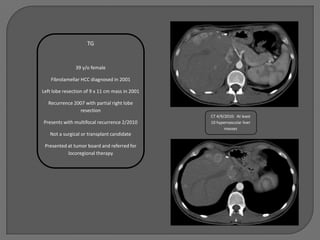

TG

39 y/o female

Fibrolamellar HCC diagnosed in 2001

Left lobe resection of 9 x 11 cm mass in 2001

Recurrence 2007 with partial right lobe

resection

CT 4/9/2010: At least

Presents with multifocal recurrence 2/2010      10 hypervascular liver

masses

Not a surgical or transplant candidate

Presented at tumor board and referred for

locoregional therapy